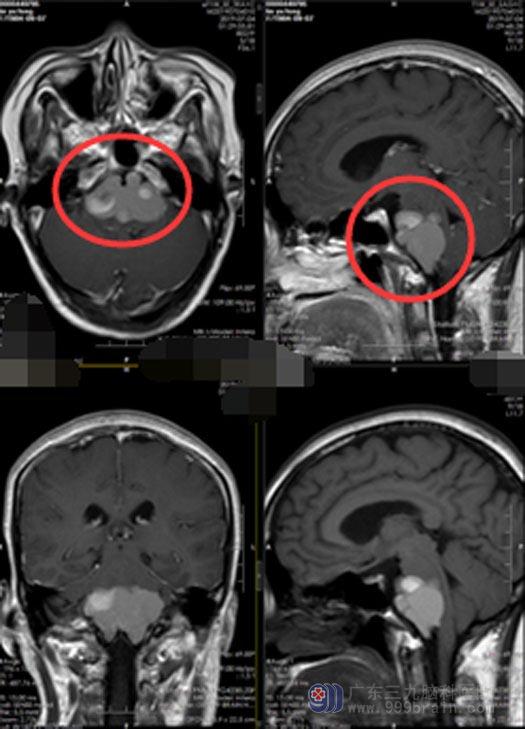

34岁的林女士一个月前突然出现阵发性的头晕头痛,视物模糊不清,有重影。她认为夏天到了,是肝火旺盛引起的。服药治疗后总不见好转,附近医院头颅MR检查提示:考虑桥前池占位并出血可能。

林女士觉得自己就是头晕头痛的小毛病,不需要处理的。回家后症状没有好转,经家属劝说和周围邻居推荐,林女士半信半疑地来到广东三九脑科医院,进一步检查考虑“桥延前池区占位性病变,考虑含有蛋白或胆固醇的囊肿类病变可能性大”。

手术顺利,麻醉清醒后林女士生命体征平稳,对答切题,视力视野正常,四肢活动自如,未出现明显神经功能障碍。复查核磁共振显示肿瘤全切,病理报告示:表皮样囊肿。